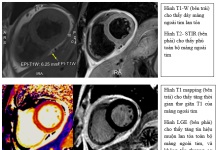

Vai trò của cộng hưởng từ tim trong hội chứng động mạch vành mạn...

3. ĐÁNH GIÁ SỐNG CÒN CƠ TIM TRONG BỆNH ĐỘNG...

1. MỞ ĐẦU